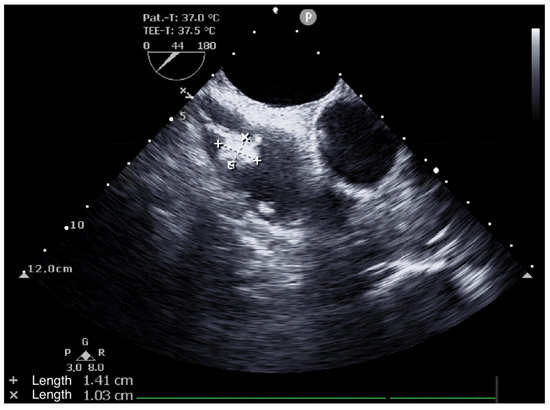

2. Case Presentation